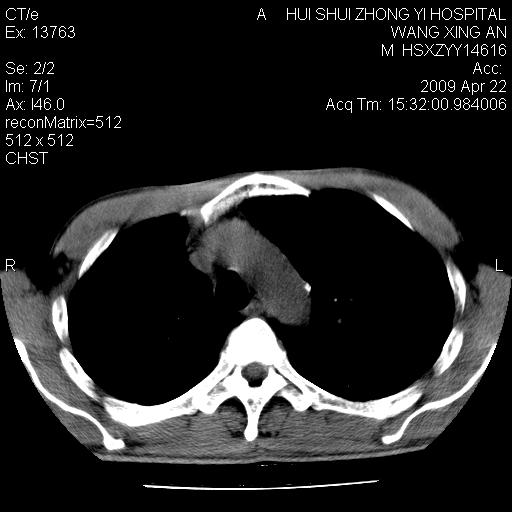

标题: CT19534:患者男、46岁咳嗽、胸痛半月。 [打印本页]

标题: CT19534:患者男、46岁咳嗽、胸痛半月。

考虑---右肺中心型肺癌继发下叶不张,少量胸水。

支持右侧中央型肺ca并右下肺不张、右侧胸腔少量积液。

1、右下肺中央型肺癌并右肺转移,右肺下叶不张。(右肺有结节影)。

2、右中上肺陈旧性肺结核(因为大多为纤维灶)。

3、右侧胸腔积液。

1、右下肺中央型肺癌并右肺转移,右肺下叶不张。(肿块围绕右肺下叶支气管生长,致管腔闭塞右肺下叶不张;右肺有结节影)。

2、右侧胸腔积液。

3、右中上肺陈旧性肺结核(右肺见纤维化病灶及点状钙化)。